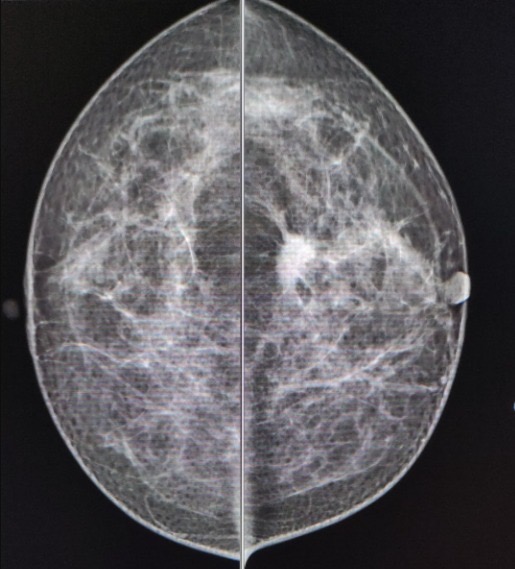

La mastografía en mujeres entre 40 y 69 años.